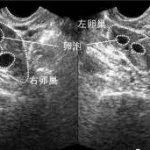

卵子采集是三代试管婴儿程序中的重要步骤之一,其费用包括女方卵泡刺激剂、卵泡穿刺抽取和镜下探查等。这部分的费用也因医院、地区和女性年龄等因素不同而有所差异。